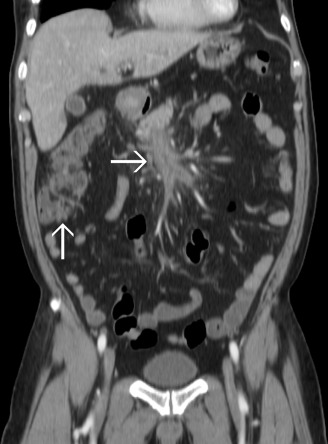

A 60-year-old man was hospitalized because of acute diverticulitis complicated with Bacteroides fragilis bacteremia. The computed tomography (CT) scan showed cecal diverticulitis with superior mesenteric vein (SMV) thrombosis ( Fig. 1 ). At that time, he received parenteral antibiotics for 2 weeks and then oral antibiotics for 1 week after discharge. Nine days later, he presented to our emergency department with progressive abdominal pain and fever. CT scan demonstrated improved diverticulitis but progressive local peritoneal inflammation around the SMV thrombosis (Fig. 2 ).

Figure 1.

The upward arrow indicates cecal diverticulitis and the rightward arrow indicates superior mesenteric vein thrombosis.